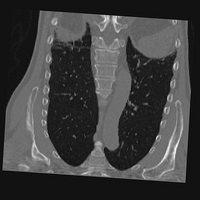

Exp. 3: Adult thorax data: To show the versatility of our approach we also apply it to adult thorax scans. For this experiment no organ specific training is performed but the whole volume is used. We evaluate reconstruction performance similar to Exp. 1 and prediction performance when is projected on an external plane, comparable to X-Ray examination using C-Arms. The latter provides insights about our method’s performance when applied to interventional settings in contrast to motion compensation problems. 60 healthy adult thorax scans were randomly selected, 51 scans used for and nine scans used for . Each scan is intensity normalised and resampled in a volume of with spacing . Using the Fibonacci sampling method, 25 sampling plane of size , evenly spaced between -50 and +50, were rotated over 500 normals. Training took approximately 20 hours for 60 epochs. Fig. 4c shows an example reconstruction result gaining 28dB PSNR with additional SVR. prediction takes approx. 20 ms/slice for this data.

0..5.3 Exp. 3:

We replicated the experiment on adult thorax data without specifically segmented organs. This approach was applied to CT acquisition, shown in Fig 13 and 14, as well as Digitally Reconstructed Radiographs generated using Siddon-Jacobs Ray Tracing shown in Fig. 16.